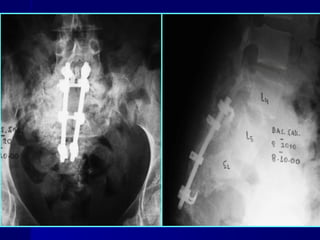

PERCUTANEOUS ILIOSACRAL SCREW FIXATION

• For unilateral sacral fractures zone I or zone II

• Under fluoroscopic control the reduction is obtained and

held by iliac screws (cannulated)

OPEN REDUCTION AND INTERNAL FIXATION